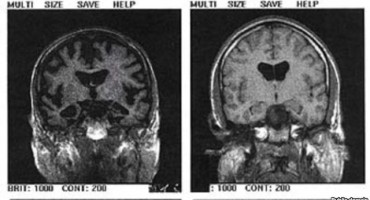

Japanski i australski znanstvenici razvili su krvni test kojim se, i prije pojave simptoma Alzheimerove bolesti na jeftin i precizan način mogu detektirati beta amiloidi, toksične bjelančevine iz…